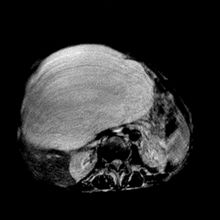

3、影像學診斷用B型超音波檢查華支睪吸蟲病患者時,在超聲像圖上可見多種異常改變,如肝內光點粗密欠均,有斑點狀、團塊狀或雪片狀,瀰漫性中小膽管不同程度擴張、膽管壁粗糙、增厚,回聲增強或膽管比例失常及枯枝狀回聲。儘管聲像圖特異性不強,但與流行病學、臨床表現及實驗室檢查對比分析,仍具一定診斷價值。

CT檢查對華支睪病診斷也有較大價值。有資料報導,在CT照片上,華支睪吸蟲膽道感染具有以下特徵:肝內膽管從肝門向周圍均勻擴張,肝外膽管無明顯擴張;肝內管狀擴張膽管直徑與長度比多數小於1:10;被膜下囊樣擴張小膽管以肝周邊分布為主,管徑大小相近,這些是特異性徵象;少數病例膽囊內可見不規則組織塊影。因此認為CT是本病較好的影像學檢查方法。